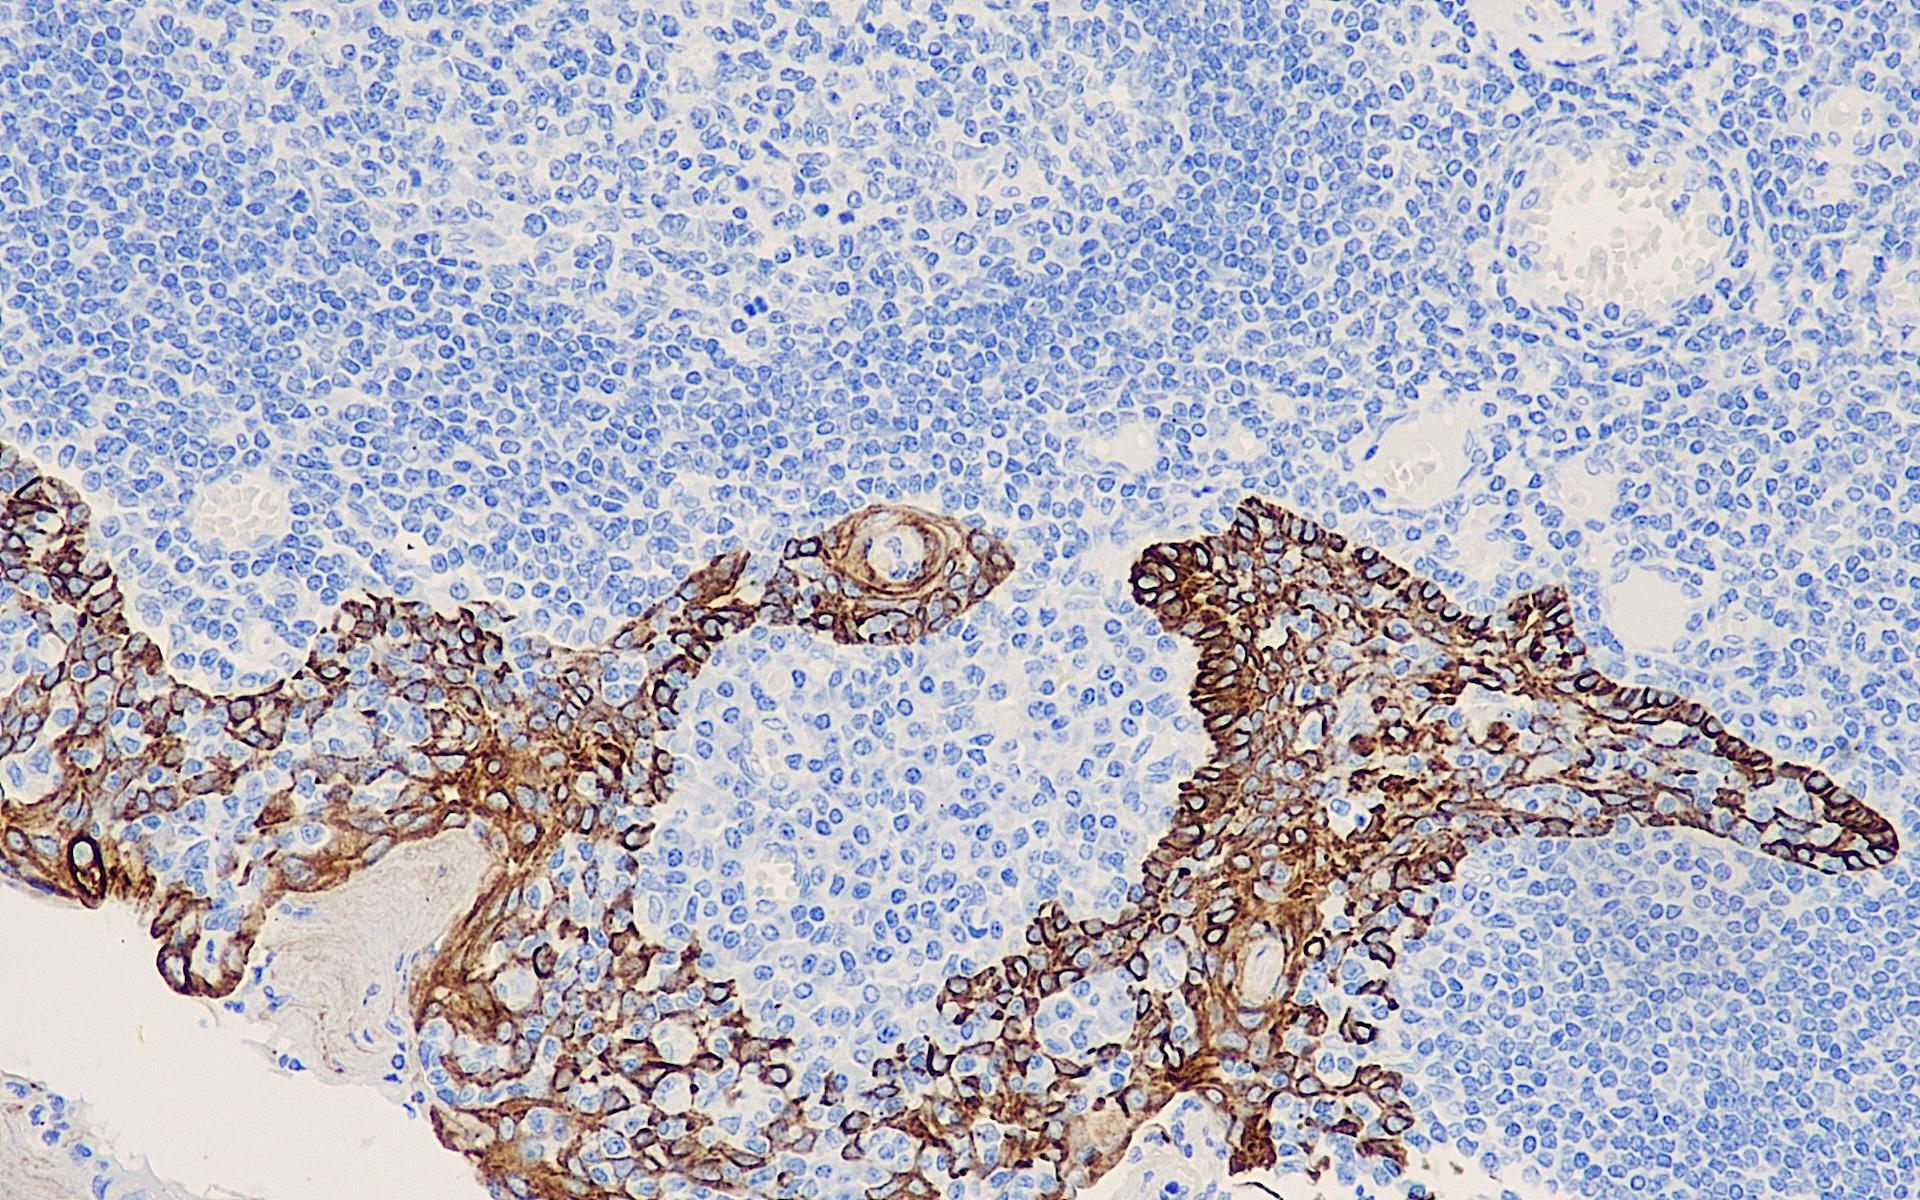

AE1/AE3 recognizes members of the acidic and basic subfamilies of cytokeratins, with the acidic members including keratins with molecular weights of 56.5, 55, 51, 50, 50′ 48, 46, 45, and 40 KDa, and the basic members including keratins with molecular weights of 65-67, 64, 59, 58, 56, and 52 KDa.AE1/AE3 is a broad-spectrum antibody to keratins that is of interest for metastatic tumors of epithelial origin.

AE1/AE3 Mixed Molecular Weight Keratin Antibody Reagent binds specifically to AE1/AE3 molecular antigens. Immunohistochemistry kits containing AE1/AE3 Mixed Molecular Weight Keratin Antibody Reagent are indicated for the precise diagnosis of metastatic tumors of epithelial origin.